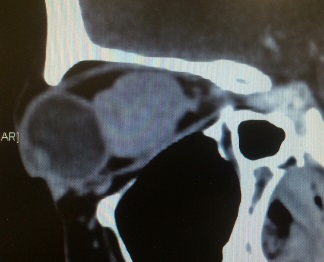

Any tumour mass can occur within the bony socket of the eye. It may occur as a primary tumour or secondary tumour (metastatic disease). It is also essential to know the difference between a benign and malignant tumour. After discussing the symptoms and signs, a detailed clinical examination and some clinical tests, Dr Nazila will order for an imaging such as CT scan or MRI and advise for surgery.

Orbital cellulitis is an orbital infection of the soft tissues within the eye socket. It is most often due to an extension of infection from nearby sinuses. It can also be caused by direct infection following local injury such as insect bite and penetrating eyelid injuries. Spread of infection from the face or teeth via blood can also be the cause. Patients may present with blurred vision, double vision, eye pain, bulging eye, eyelid swelling and redness. Fever may accompany the other symptoms. Diagnosis is based on history, clinical examination and imaging such as CT scan or MRI. First line of treatment is systemic antibiotics and sometimes surgical drainage may be required.